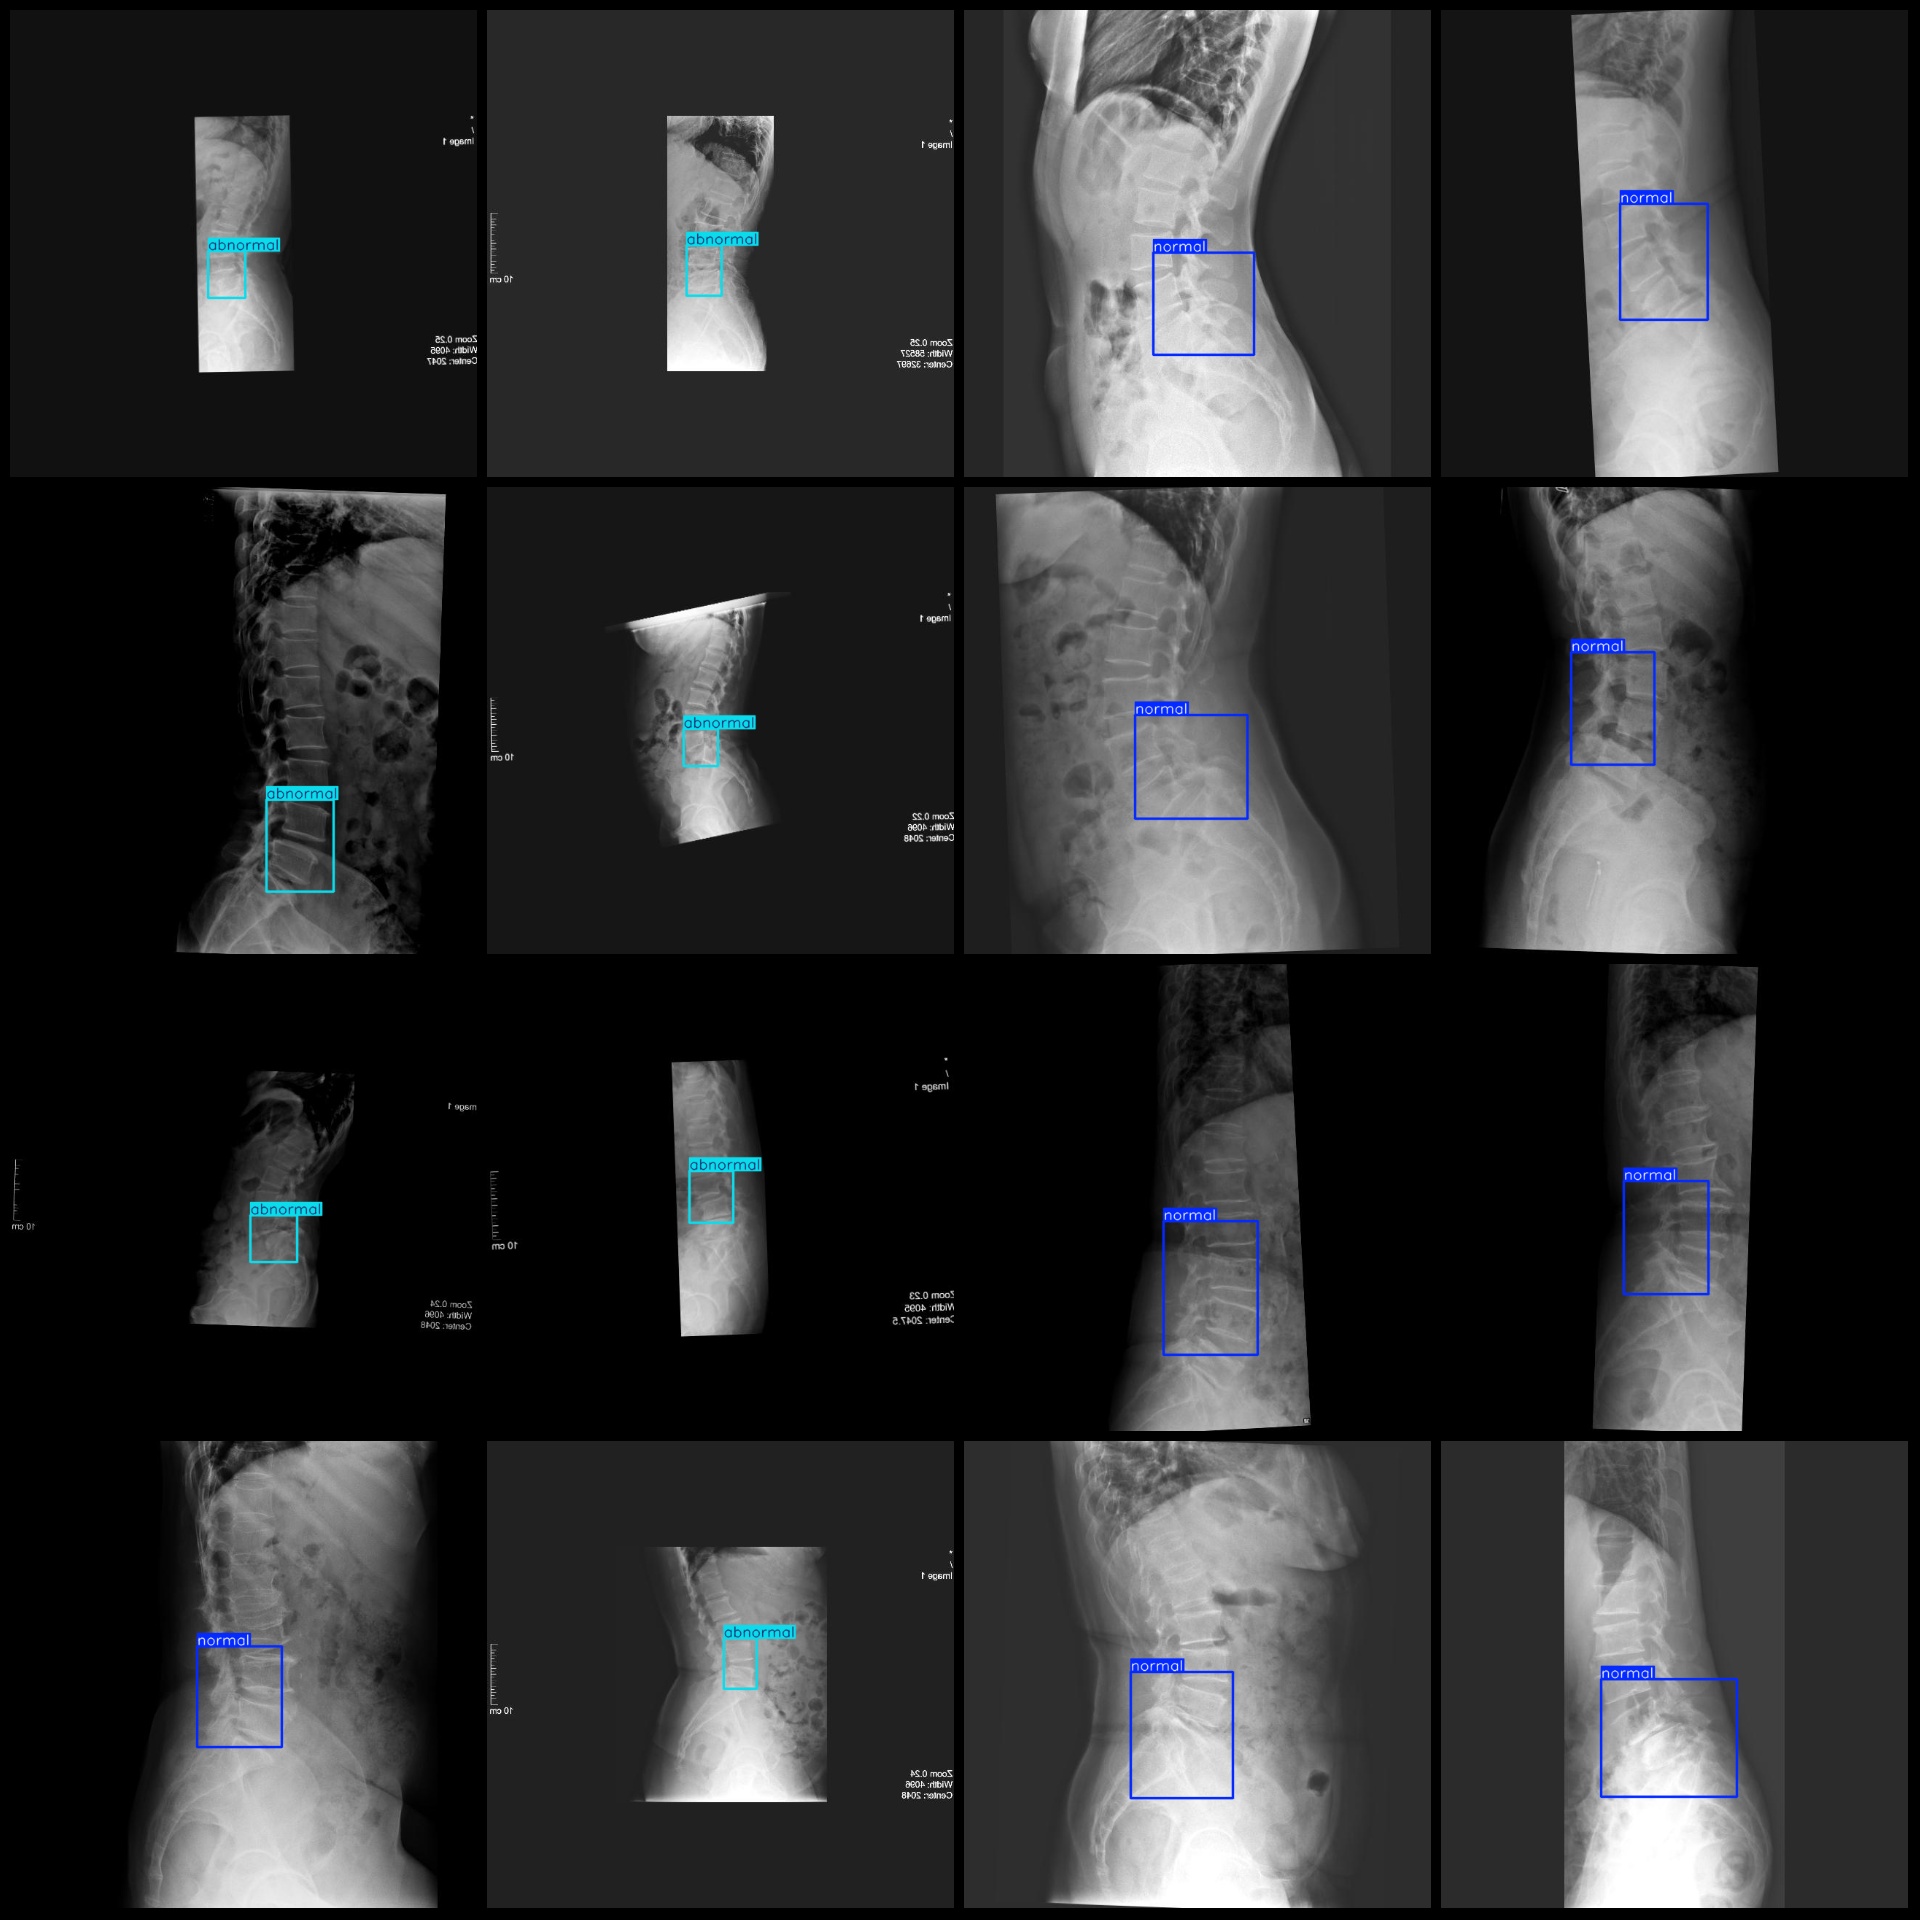

标注类别名称(注意yolo格式类别顺序不和这个对应,而以labels文件夹classes.txt为准):["abnormal","normal"]

abnormal 框数 = 439

normal 框数 = 822

总框数:1261

abnormal 占有图片数 = 439

normal 占有图片数 = 822

图片分辨率:640x640

图片预览:

标注例子: